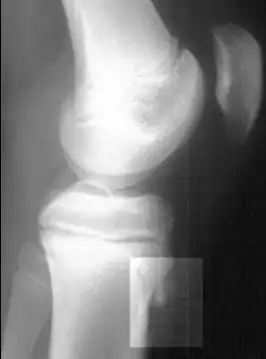

![]() Radiografía lateral de la rodilla demostrando fragmentación del tubérculo tibial, con tejido sobreabundante | ||

Una radiografía de hueso puede ser normal o puede mostrar inflamación o daño a la espina tibial. Las radiografías se usan muy poco, a menos que el médico quiera descartar otras causas del dolor.

Rayos X mostrando la enfermedad de Osgood-Schlatter